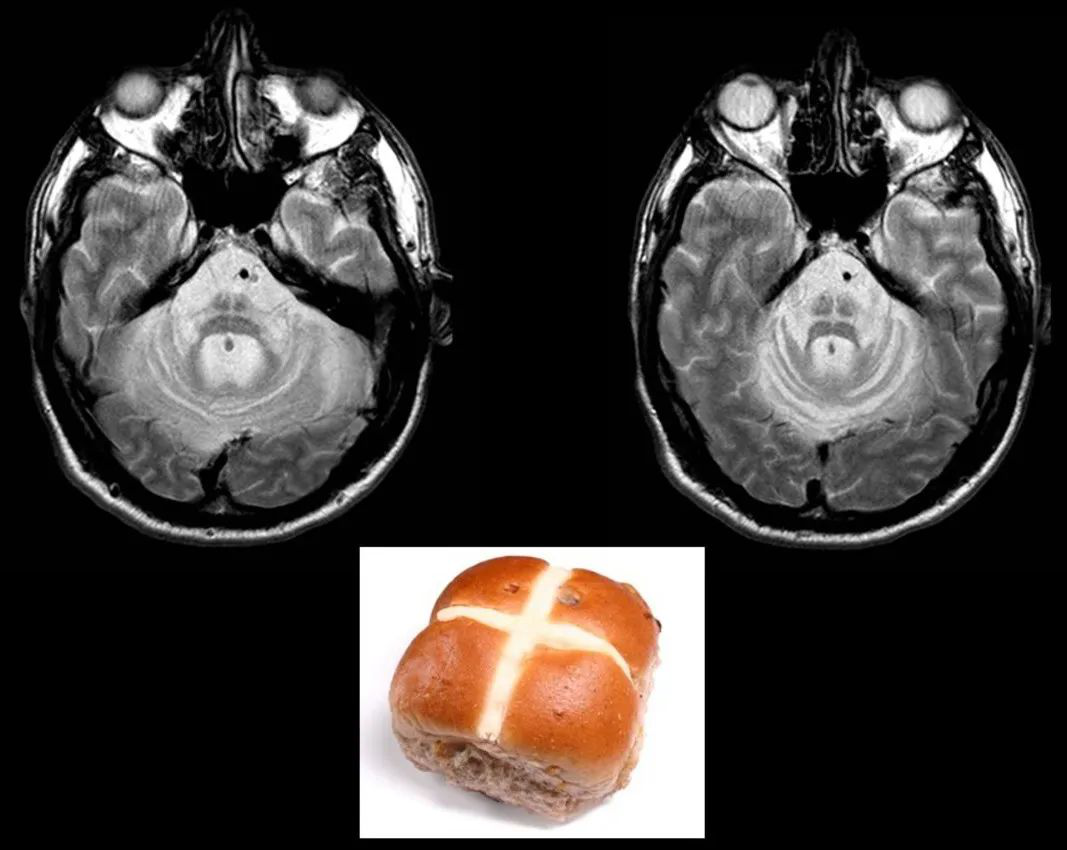

MSA-C 型的 MR 常出現(xiàn):橄欖、橋腦、小腦中腳和小腦的萎縮,橫軸面上橋腦 T2WI 交叉樣高信號,即所謂的「十字征」,是診斷 MSA-C 的較特征性的表現(xiàn)?!甘终鳌沟牟±韺W基礎(chǔ)為橋腦核及其發(fā)出的通過小腦中腳到達小腦的纖維 (橋橫纖維) 變性和神經(jīng)膠質(zhì)增生,T2WI 信號增高。有學者認為,先出現(xiàn)「垂線征」(需要仔細觀察),后出現(xiàn)「十字征」。但「十字征」并非 MSA-C 型所特有,其他疾病比如遺傳性小腦共濟失調(diào)也可出現(xiàn)。

欖、橋腦、小腦中腳和小腦的萎縮

橄欖、橋腦、小腦中腳和小腦的萎縮,出現(xiàn)「十字征」